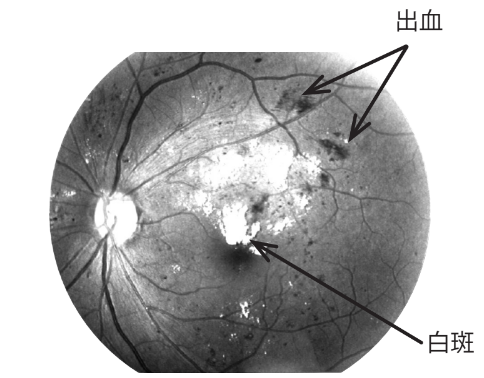

糖尿病網膜症の眼底は、初期では出血や白斑が出現します。

初期の糖尿病網膜症の例(左眼)